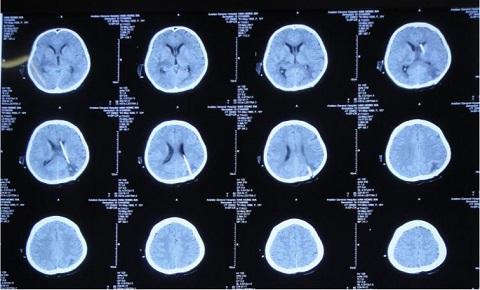

5月22日给予患者行侧脑室外引流术,术后脑脊液色黄微浊。

6月20日,引流脑脊液仍然色黄浑浊,复查头CT环池、鞍区仍然密度升高、间隙消失。

8月16日,患者脑脊液仍然色黄浑浊,复查增强MRI现实四叠体池区、鞍区、环池内多发结核脓肿。